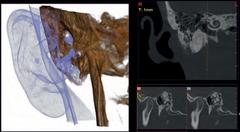

Maximum flexibility for your diagnoses Hyperion X9 pro is fully configurable and its modular and scalable design makes it possible to transition from a basic to a more advanced version in an easy and costeffective manner. An extraordinary platform that adapts to the needs of your dental practice thanks to the 2D PAN/CEPH sensor, which can be easily relocated, and the reversible teleradiographic arm which can be installed on both sides Moreover, the standard 2D sensor can be replaced with the innovative direct conversion DCIII sensor to provide SuperHD images with low doses The most versatile extra-oral 3-in-1 imaging device on the market. Perfect for ultra-high quality 2D and 3D exams with very low doses

FOVs with a 10 cm diameter are essential for the study of impacted third molars because, in an adult of medium build, the distance between the third molars on the left and right, including the respective roots, the alveolar process and the surrounding bone, is at least 9 cm Reduced fields of view are useful when analysing impacted or supernumerary teeth in order to restrain the dose to the region of interest For a correct treatment planning it is indeed crucial to determine the actual position (vestibular or palatal) This is only possible with a 3D analysis, even at a very low dose, with the QuickSCAN protocol The complete 13 x 16 cm field of view allows for an accurate assessment of the upper airways, which is often useful to complete the investigation for an orthodontic treatment that does not neglect ENT problems.

Maxillary sinuses

Frontal or left/ side view, with optimised trajectory